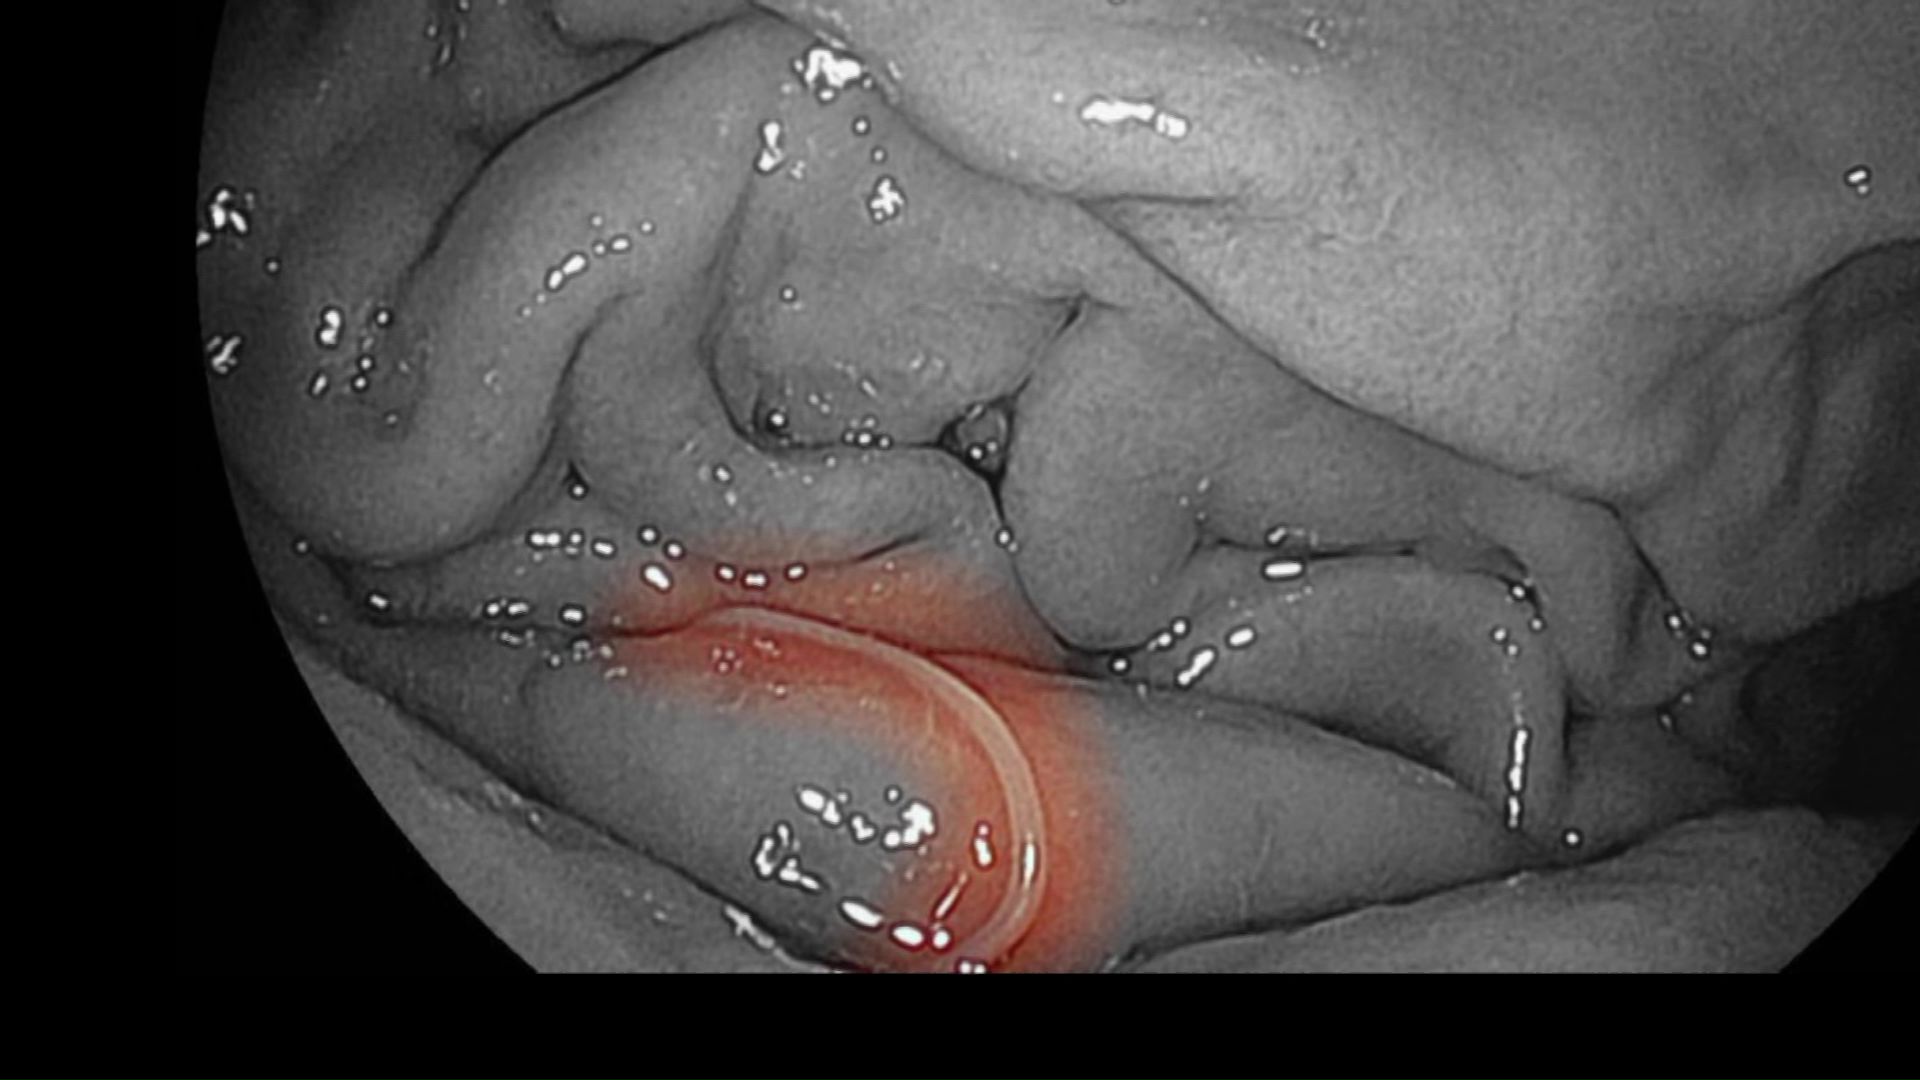

どうにか病院に行って胃カメラで検査すると、モニターに映ったのは白い糸くずのようなアニサキスでした。

胃カメラを使って摘出しましたが、痛みは数日続きました。